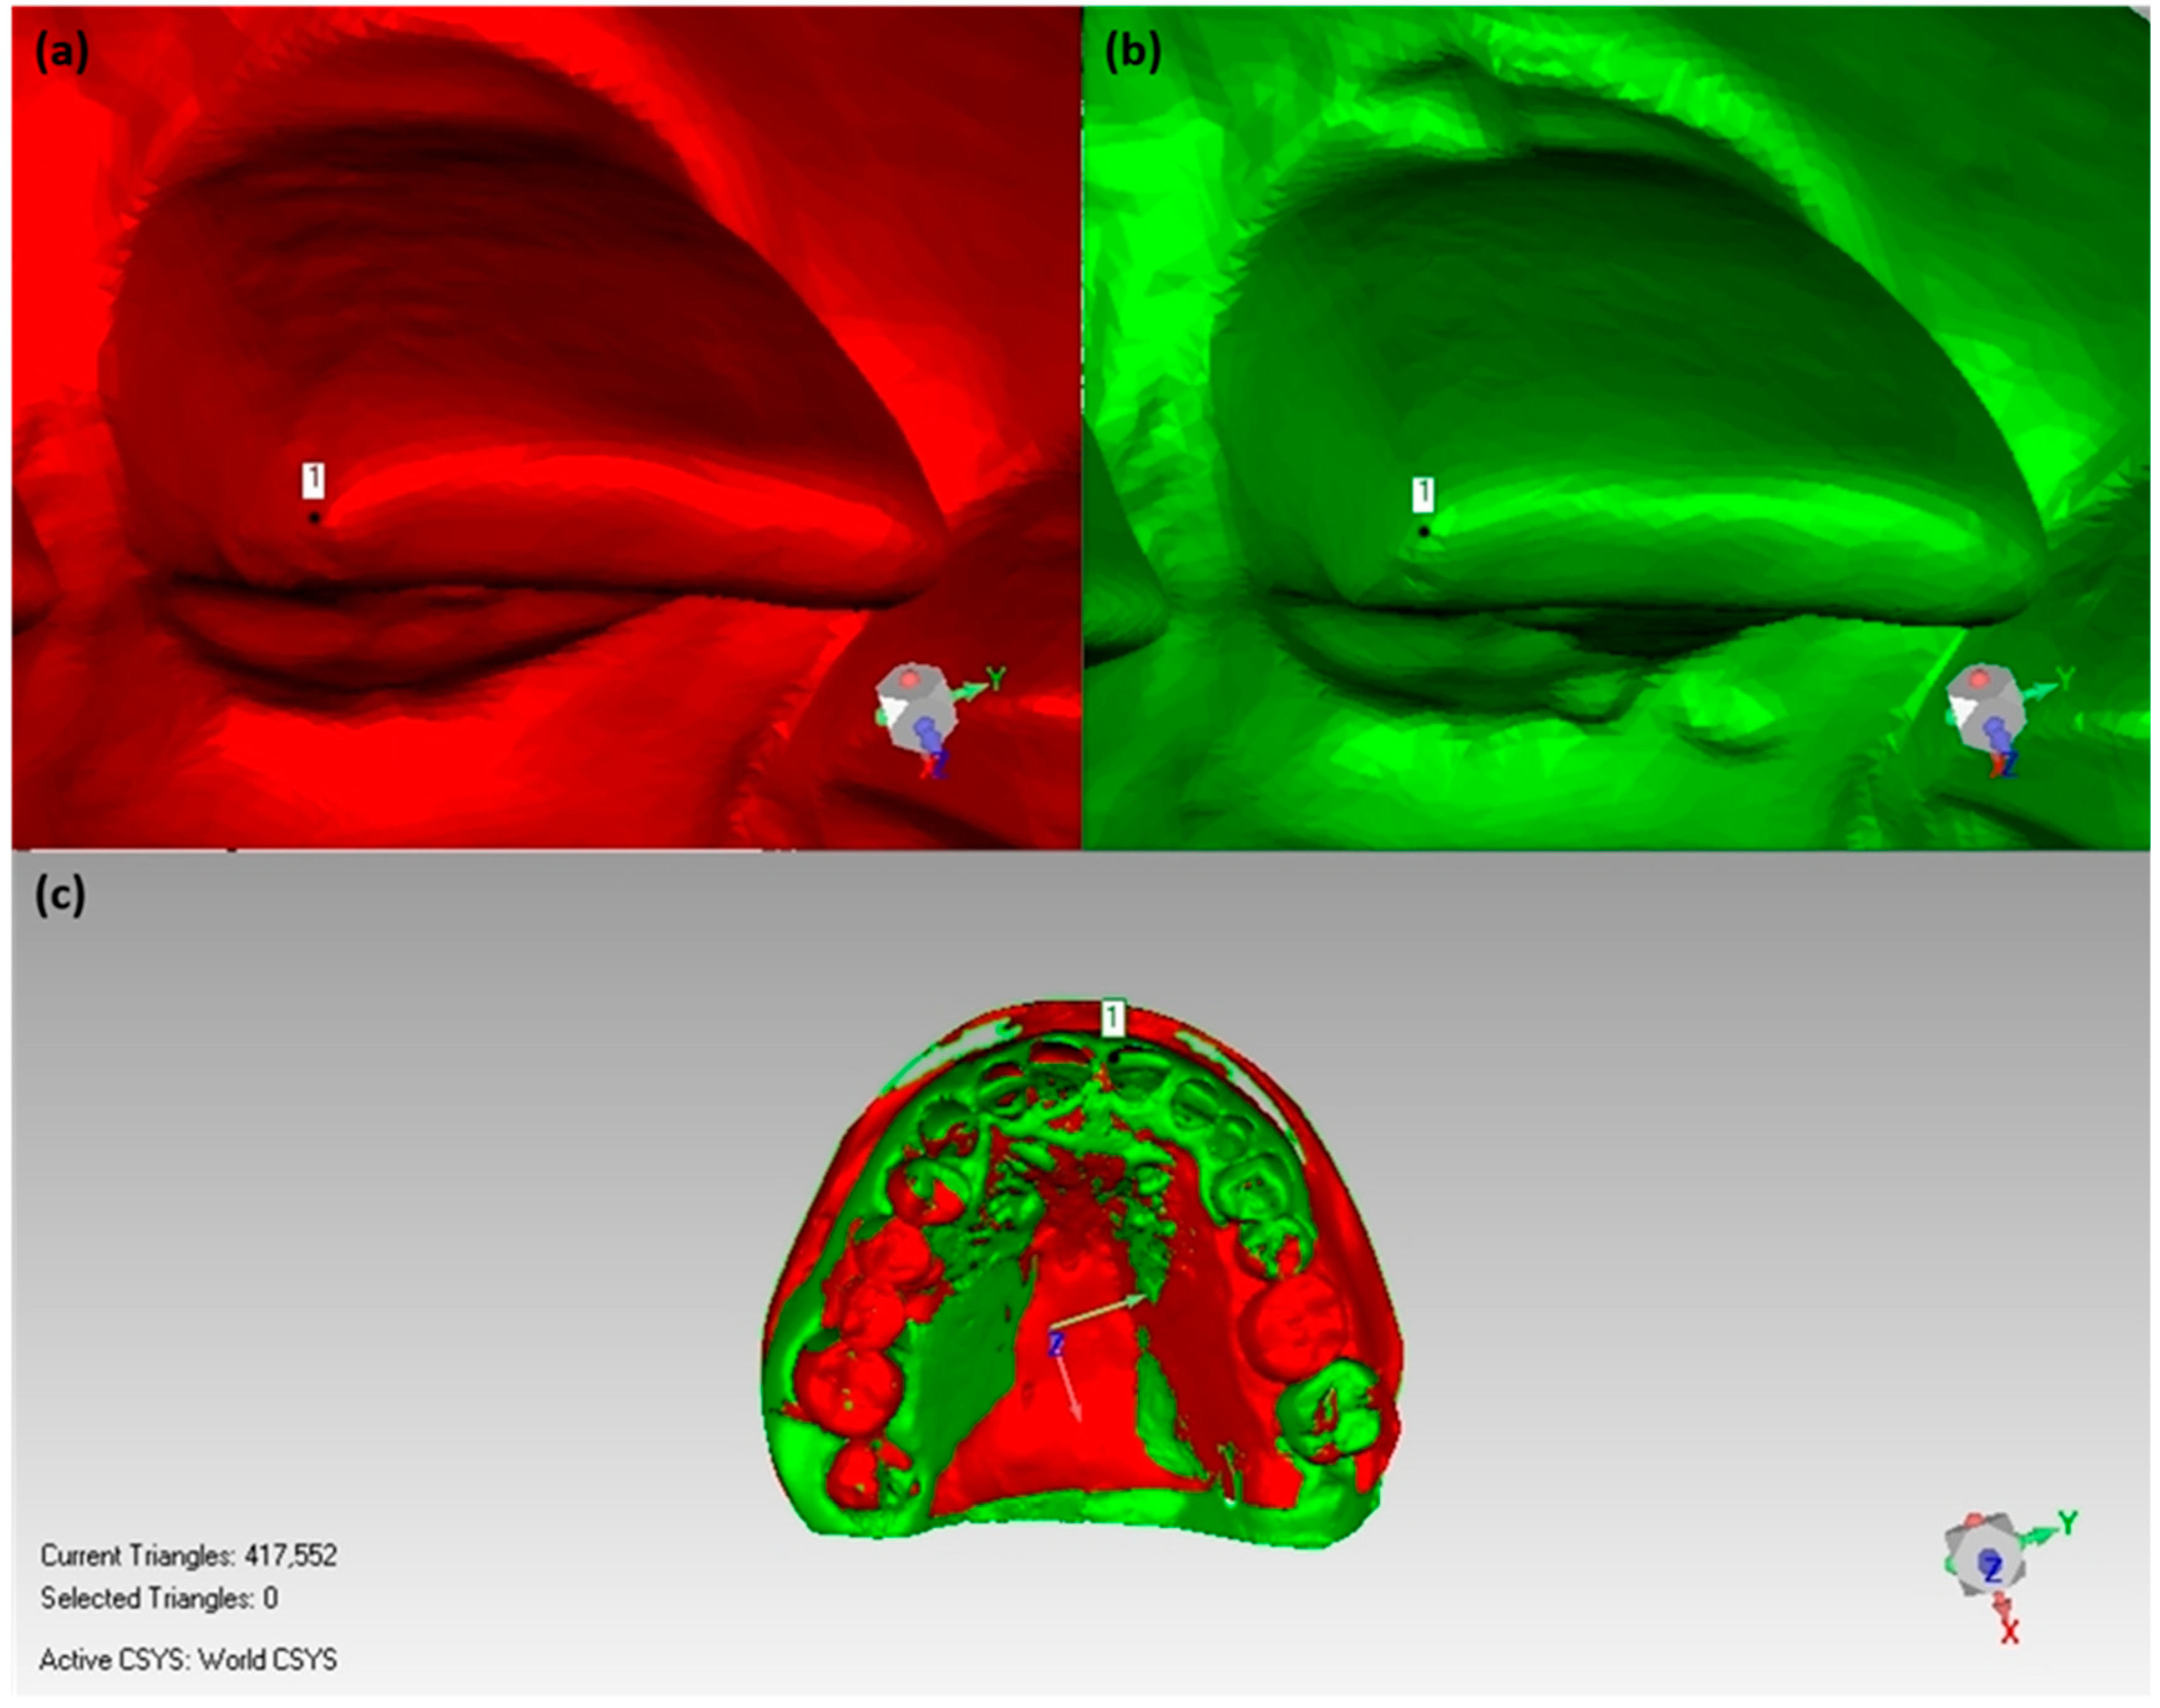

2.6. Volumetric Assessment of Soft and Hard Tissue

2.6.1. Volume Calculation for Soft Tissue/Stone Cast Measurement

2.6.2. Bone Volume Calculation/Radiographic Assessment

3.2. Results of Volumetric Analysis